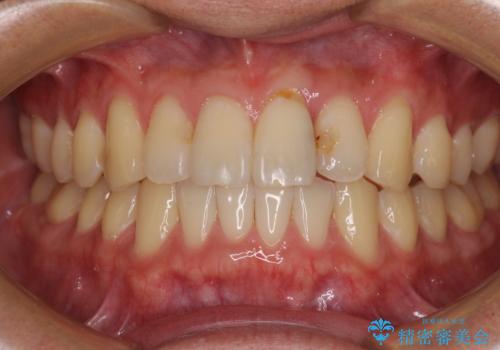

全顎的なクロスバイト 補助装置を用いてワイヤー矯正

- 2年1ヶ月

- 治療費の目安: 105万円(税込)費用は治療当時の料金となります